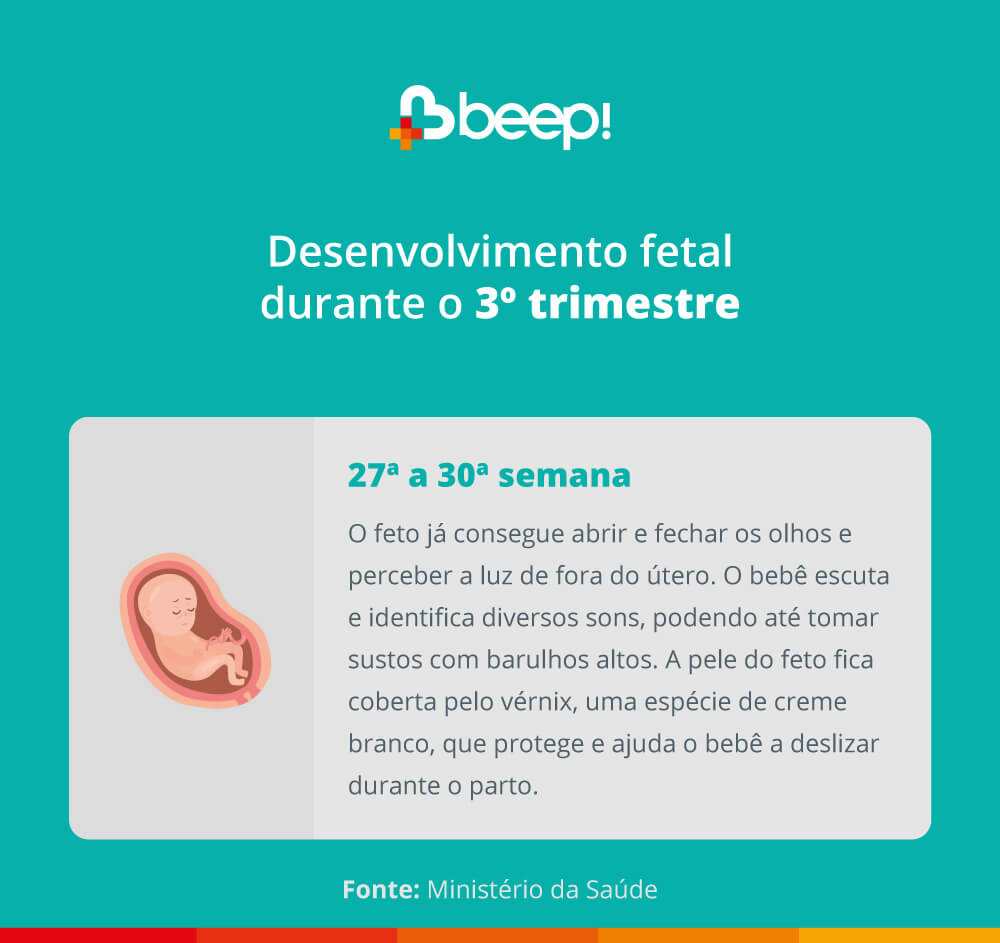

3º trimestre de desenvolvimento do feto

É a reta final da gravidez. Hora que o seu bebê está pertinho de chegar! Nesse período, alguns fetos viram de cabeça para baixo.

Abaixo, vamos trazer as informações sobre esse último período de gestação. Confira!